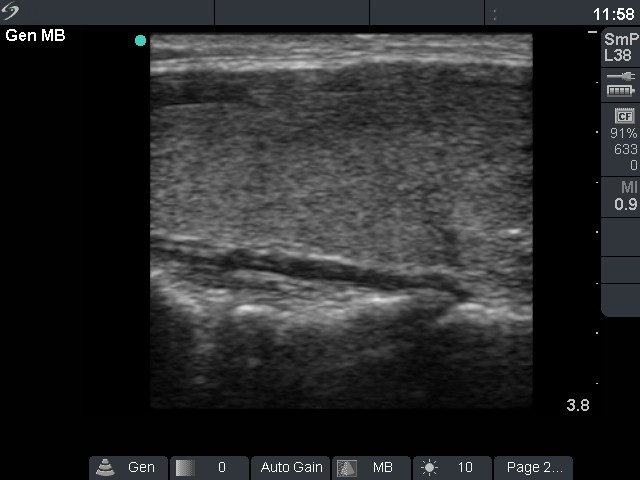

Follow-up investigation 18 months after first visit (ultrasonographic picture 2)

Patient on daily 5 mg methimazole therapy in euthyroid state

Right lobe, longitudinal scan.